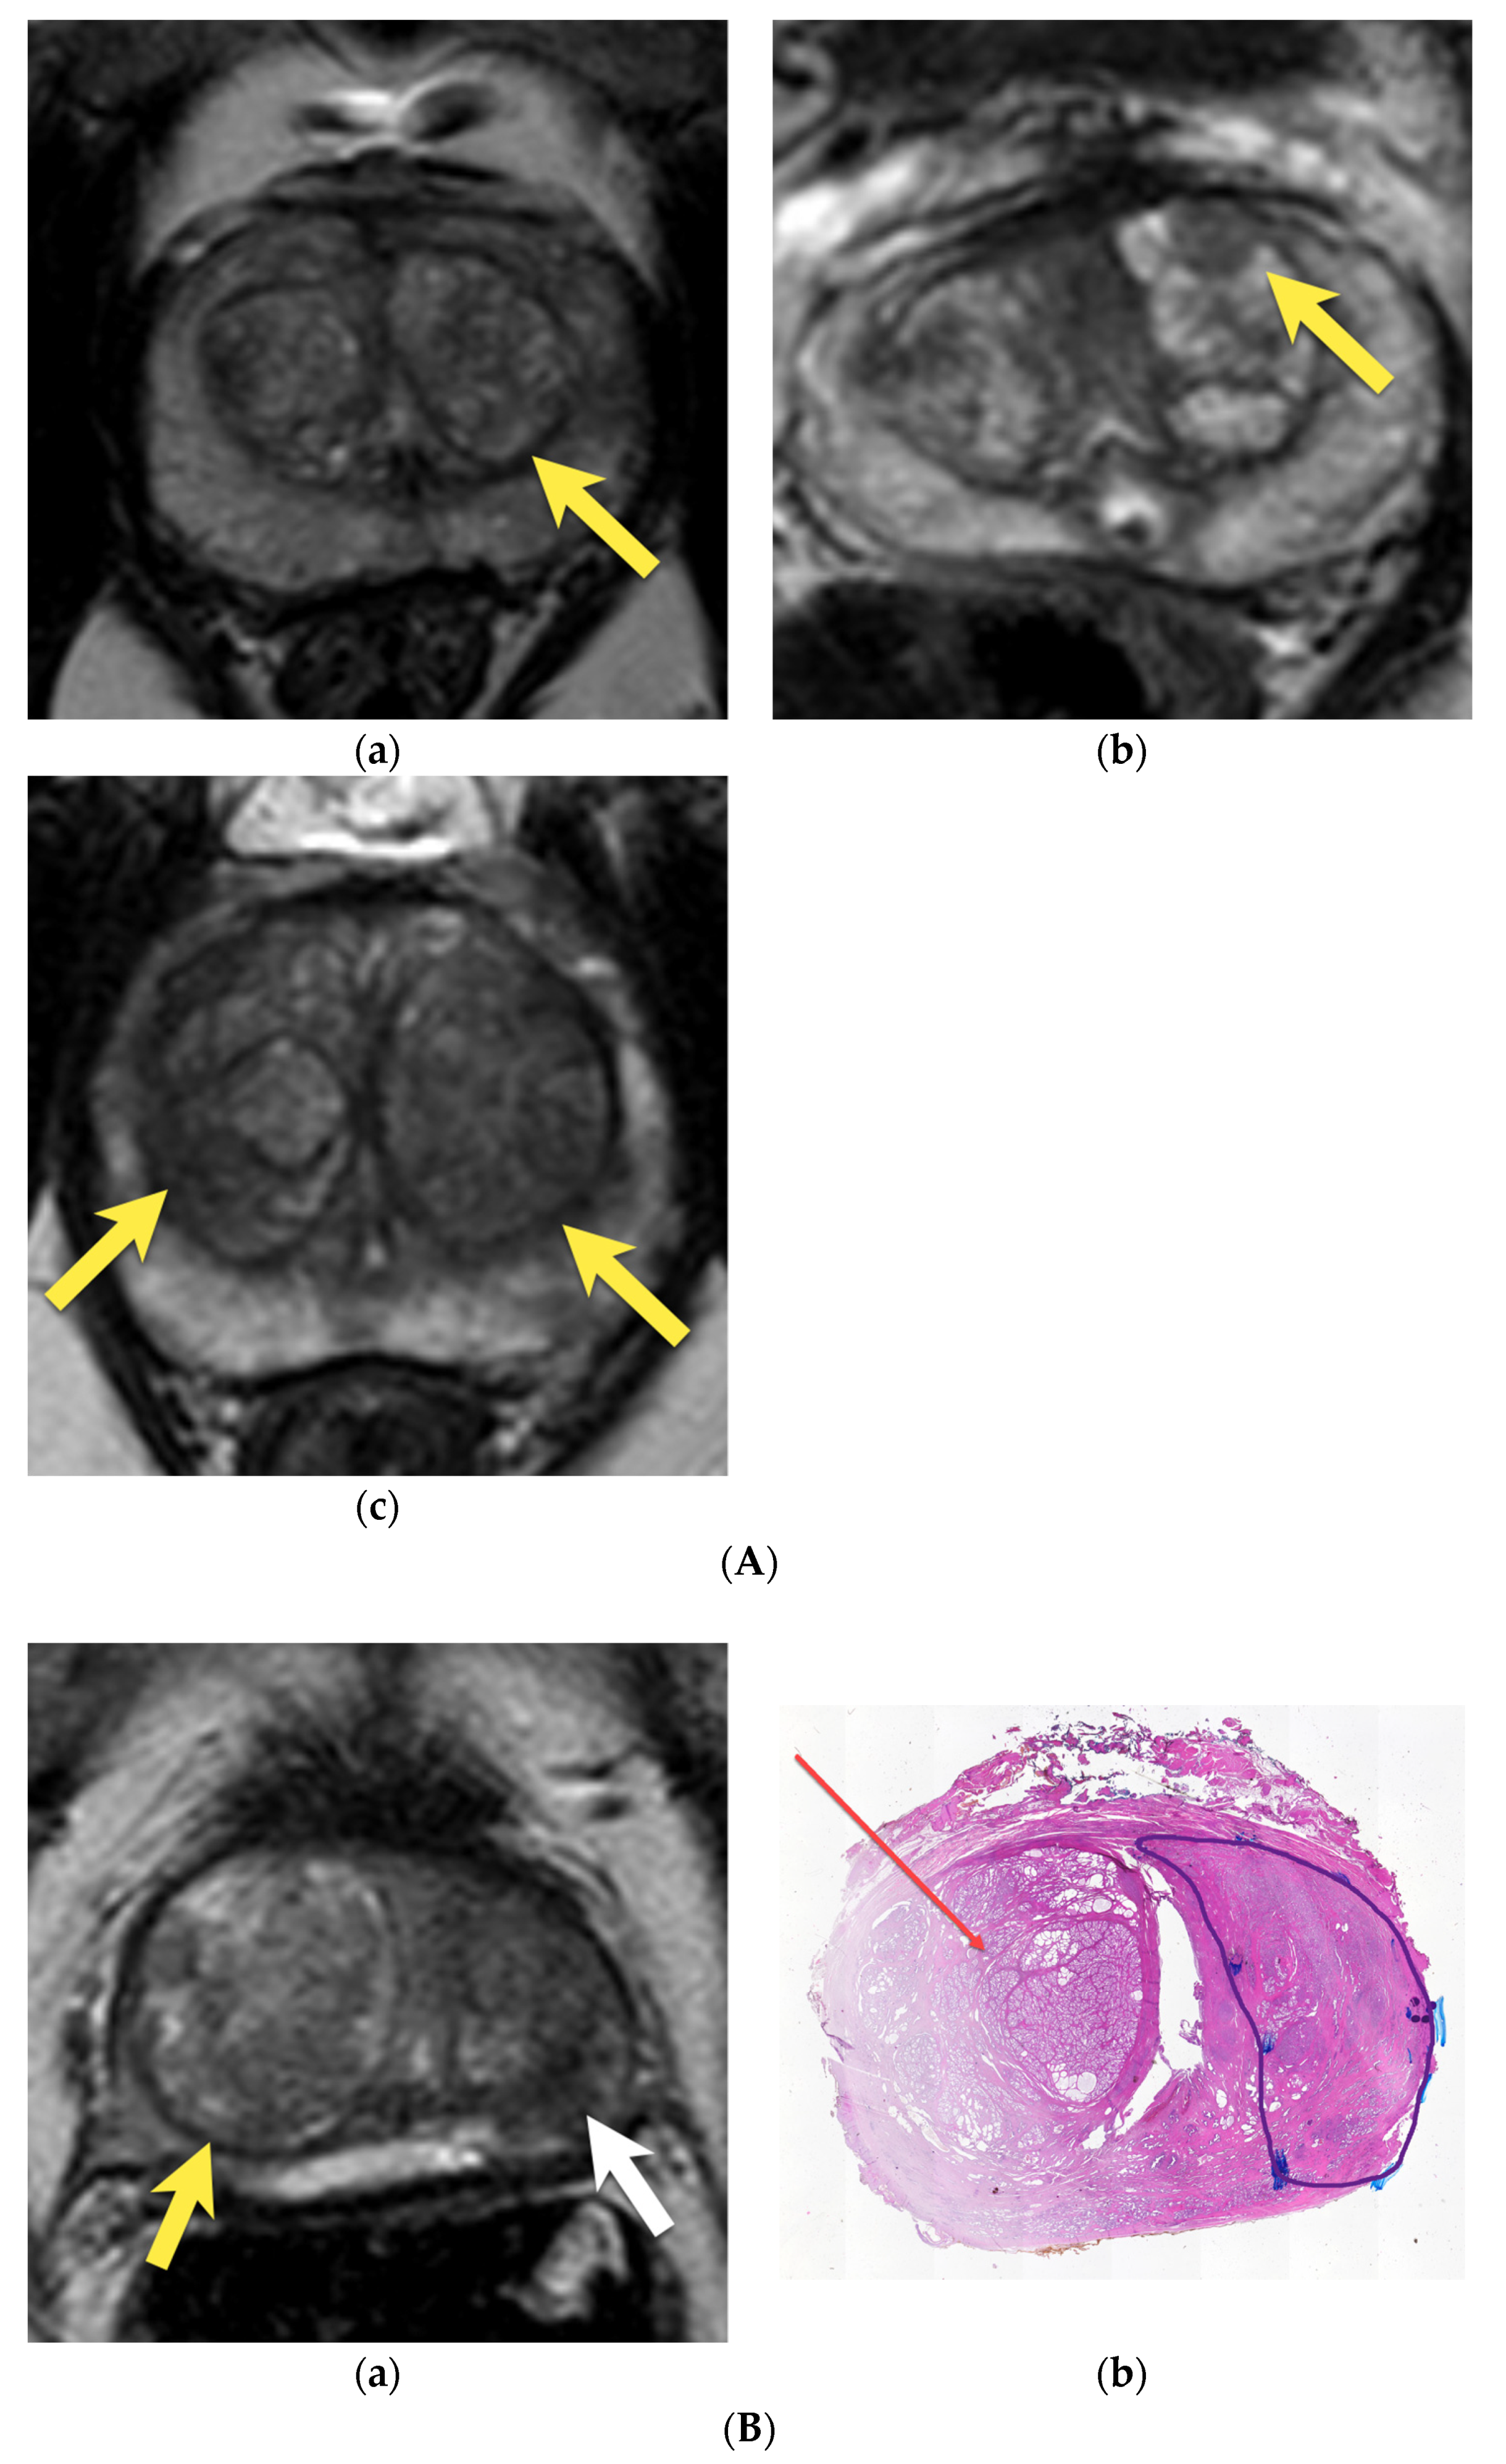

7. Ectopic BPH Nodules

9. Prostatitis

10. Prostatic Abscess